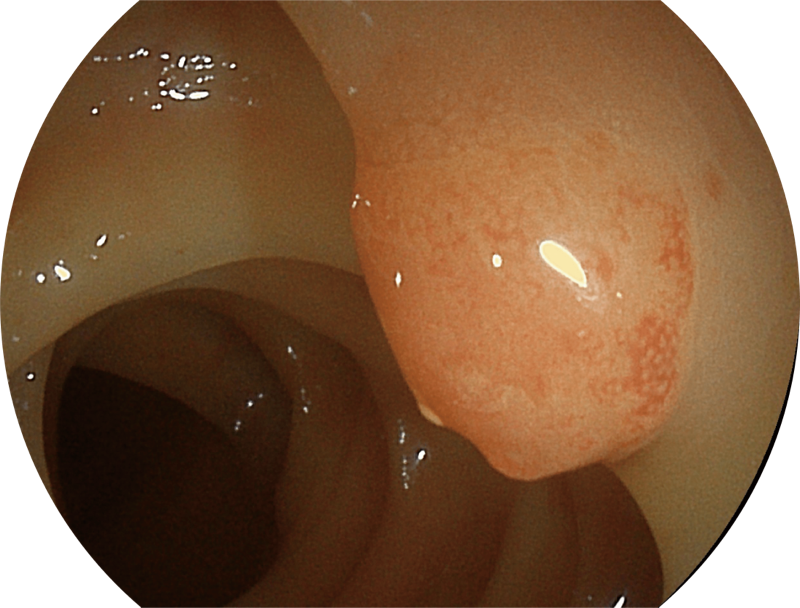

百万级像素高清传感器,1080P全高清视频信号输出,图像清晰。

(Versatile Intelligent Staining Technology)

能够凸显黏膜浅层血管轮廓和黏膜表面微结构,适用于中、近景观察下的早癌精确诊断。